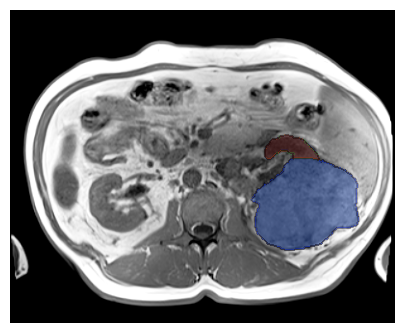

Purpose: To introduce a deep learning model capable of multi-organ segmentation in MRI scans, offering a solution to the current limitations in MRI analysis due to challenges in resolution, standardized intensity values, and variability in sequences. Materials and Methods: he model was trained on 1,200 manually annotated MRI scans from the UK Biobank, 221 in-house MRI scans and 1228 CT scans, leveraging cross-modality transfer learning from CT segmentation models. A human-in-the-loop annotation workflow was employed to efficiently create high-quality segmentations. The model's performance was evaluated on NAKO and the AMOS22 dataset containing 600 and 60 MRI examinations. Dice Similarity Coefficient (DSC) and Hausdorff Distance (HD) was used to assess segmentation accuracy. The model will be open sourced. Results: The model showcased high accuracy in segmenting well-defined organs, achieving Dice Similarity Coefficient (DSC) scores of 0.97 for the right and left lungs, and 0.95 for the heart. It also demonstrated robustness in organs like the liver (DSC: 0.96) and kidneys (DSC: 0.95 left, 0.95 right), which present more variability. However, segmentation of smaller and complex structures such as the portal and splenic veins (DSC: 0.54) and adrenal glands (DSC: 0.65 left, 0.61 right) revealed the need for further model optimization. Conclusion: The proposed model is a robust, tool for accurate segmentation of 40 anatomical structures in MRI and CT images. By leveraging cross-modality learning and interactive annotation, the model achieves strong performance and generalizability across diverse datasets, making it a valuable resource for researchers and clinicians. It is open source and can be downloaded from https://github.com/hhaentze/MRSegmentator.